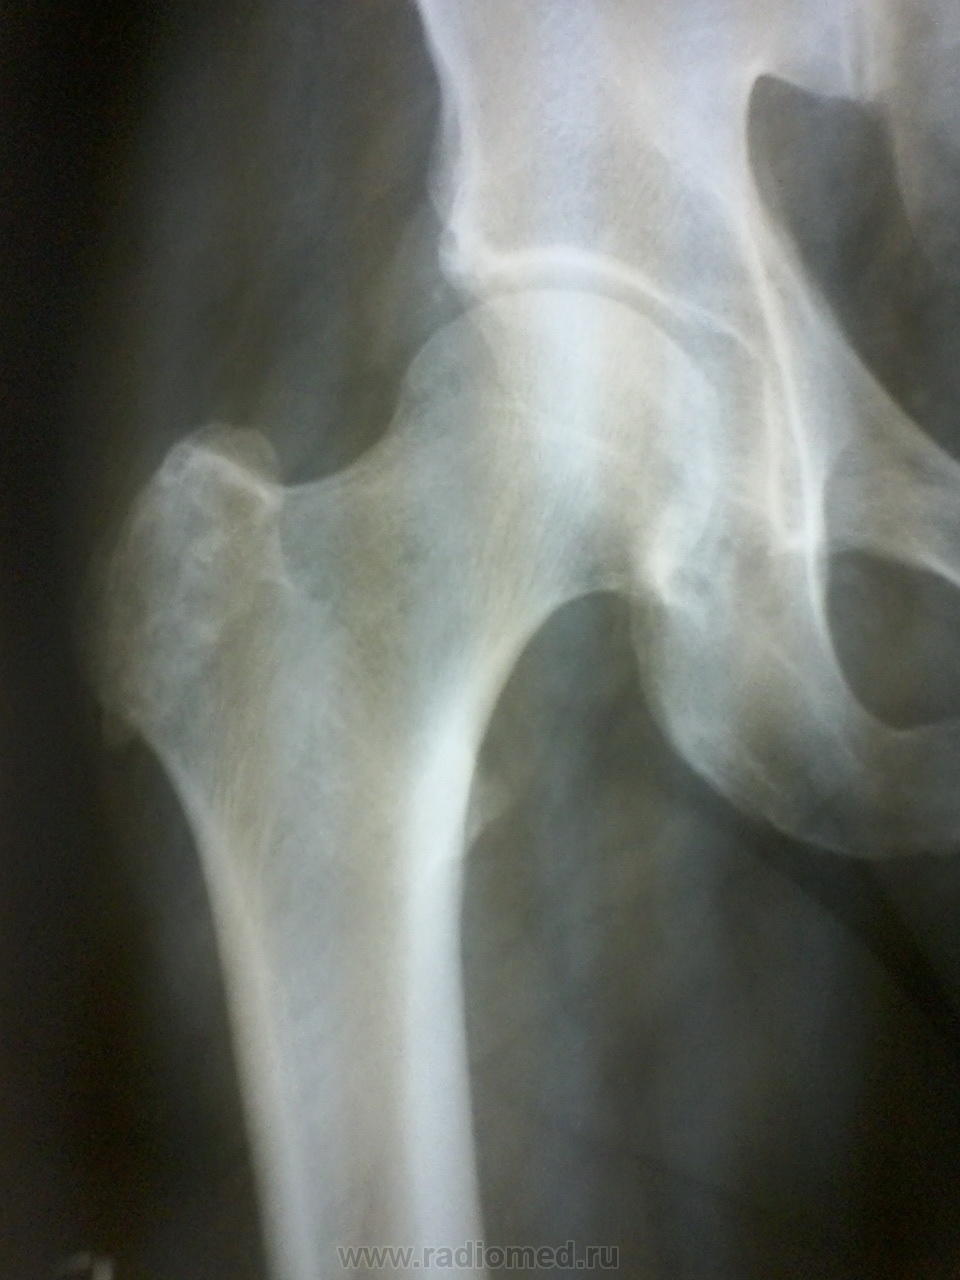

Я бы предположил хондрому, рекомендована КТ тазбедренного сустава, для уточнения характера изменений( даже если предположить, что имеет место образование кости, если честно, не вижу признаков злокачественности).

написала хондрому, контроль через полгода (, думаете надо было КТ рекомендовать ?

Для начала - так хотя бы с отведением снимок...а то вдруг там и "хондромы" то никакой не окажется)))))

Согласен, может, и не оказаться. И если бы не крыша вертлужной... К ней глаз цепляется. Какая-то она обкусанная для такого возраста. Если болит, отправил бы на дообследование. Пусть и её тоже смотрящий там поглядит!)

Намекаете на хондрому?.. А как Вам верхне-наружный отдел вертлужной впадины - может, и он ей задет?..

а сколько средних лет мужчине? опухоль хрящева,я на сколько выдно по снимку, скорее всего хондросаркома

Ну, есть обызвествления мягких тканей.

Я бы написал остеосклероз большого вертела.. и ктшка

Не помню точно, 50-55